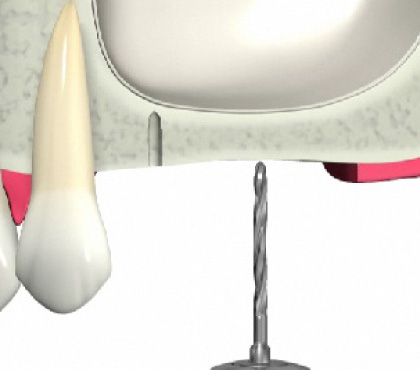

ソケットリフト方法

歯肉を切開します。

骨をドリルで切削します。

上顎洞の壁を押し上げます。

骨の材料を充填します。

インプラントを埋入します。